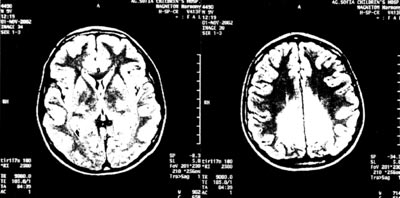

Εικόνα 2.

ΜRΙ εγκεφάλου.

Επιδείνωση αρχικών ευρημάτων και κατάληψη πρόσθιων περιοχών.

Κατά τον προγραμματισμένο επανέλεγχο του αγοριού και του μικρότερου πάσχοντος αδελφού του, 5 μήνες μετά (το Φεβρουάριο του 2003), ενώ ο δεύτερος δεν παρουσίασε διαφοροποίηση, ο ασθενής μας παρουσίασε κατά τη νευρολογική εκτίμηση ήπια πυραμιδική συνδρομή στα κάτω άκρα και στον απεικονιστικό έλεγχο του εγκεφάλου με ΜRΙ, επιδείνωση των ευρημάτων και κατάληψη και πρόσθιων περιοχών του εγκεφάλου (εικόνα 2).